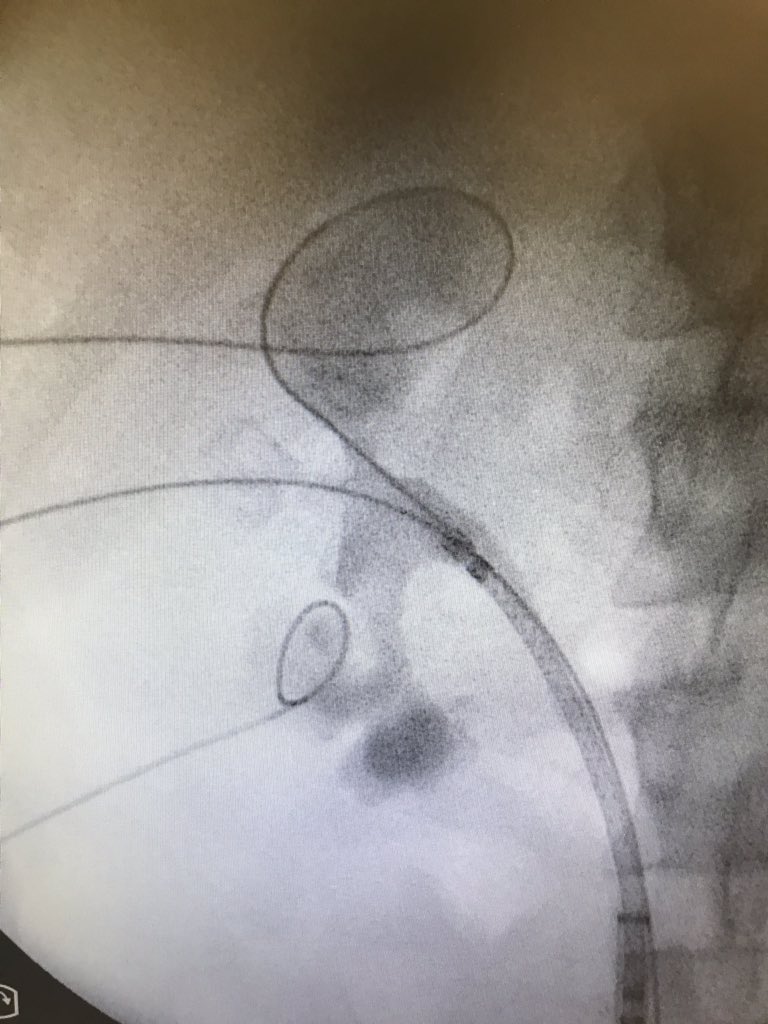

What a nigthmare…perfect surgery #ECIRS but at the end BROKEN ureteral (multiple uses) fortunately it could be removed without complications for the patient... @dr_karian @drsaid_urologia @alexfige86 @urojavo @MSGONZALEZURO @VicentiniUro @cescernesto